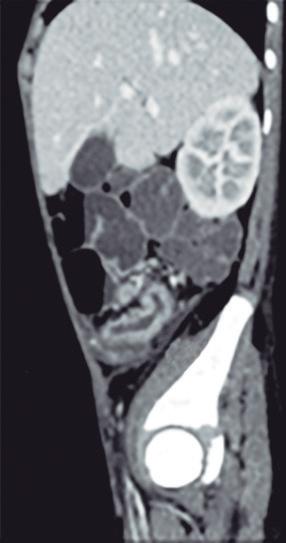

Evaluación de la dinámica de apertura de la unión esofagogástrica

Una fortaleza clave de la planimetría FLIP es su capacidad para cuantificar la dinámica de apertura de la UEG. Las métricas manométricas tradicionales, como la presión integrada de relajación (IRP), infieren la relajación de la UEG basándose en la presión intraluminal durante la deglución. En contraste, la FLIP mide directamente la apertura mecánica de la UEG bajo distensión, integrando de forma simultánea los efectos del tono del esfínter esofágico inferior, la función del diafragma crural y la complacencia de la pared esofágica.

La apertura de la UEG se evalúa mediante dos parámetros principales: el índice de distensibilidad de la UEG (DI-UEG), calculado como el área transversal mínima dividida por la presión intrabalón, y el diámetro máximo de la UEG alcanzado durante la distensión. Estas métricas han sido validadas frente al esofagograma baritado cronometrado y en relación con resultados clínicos, demostrando asociaciones sólidas con la obstrucción clínicamente relevante.9, 11

Según los umbrales establecidos, la apertura de la UEG puede categorizarse como normal, limítrofe o reducida. La apertura normal se define por un DI-UEG ≥ 2,0 mm²/mmHg con un diámetro máximo ≥ 16 mm, mientras que la apertura reducida se define por un DIUEG < 2,0 mm²/mmHg con un diámetro máximo < 12 mm. La apertura limítrofe incluye valores intermedios que no cumplen criterios para ninguna de las dos categorías.12

Es fundamental interpretar la apertura de la UEG en el contexto de la respuesta contráctil esofágica. Una UEG mecánicamente adecuada puede, no obstante, generar obstrucción funcional del tránsito del bolo en pacientes con peristalsis ausente o gravemente deteriorada, lo que subraya la necesidad de una interpretación integrada y contextualizada, en lugar de basarse en métricas aisladas.